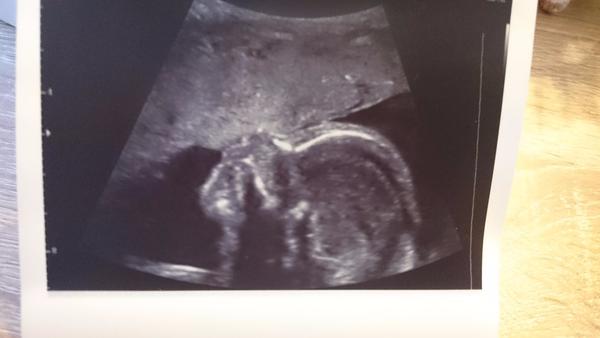

Ahojte 🙂 taak nastastie vsetko v poriadku 😉 malinke rastie ako z vody 😇 pani doktorka nam ukazala tvaricku srdiecko skontrolovala aj chrbatik nozicky 🙂 este aj celu dlan bolo vidno aj take malinke chodidielko 😍 aaa konecne vieme co to zblnkoce v brusku 🙂 mame chlapceka 😍 ❤ mame aj fotecku 'ruka hore' 😀 😀 😍

Podľa pani doktorky má moje bábätko ukazkovu citujem "šušku" 😀 takže máme sa pripraviť na 1000% dievčatko. Veľmi sa tešíme. Termín 7.7.2017. pridávam fotecku tej mojej herečky.